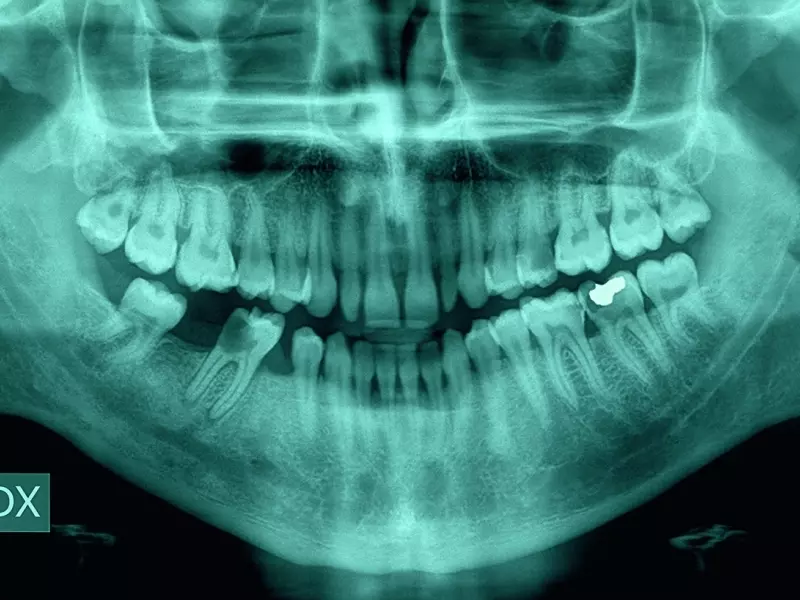

Nowoczesna stomatologia odtwórcza wykorzystuje materiały połączone adhezyjnie ze szkliwem i zębiną, których przezierność i estetyka są porównywalne do naturalnych tkanek zęba. W sposób niekwestionowany wyznacza ona nowe standardy w minimalnie inwazyjnej stomatologii rekonstrukcyjnej. Wiązanie adhezyjne jest fundamentem tej techniki, łącząc ze sobą substraty określane adherentami. W stomatologii są nimi szkliwo oraz zębina, na które nakładany jest środek adhezyjny łączący odbudowę kompozytową lub ceramiczną. Rozwój tej dziedziny stomatologii nastąpił dzięki badaniom Buonocore, który pierwszy w latach 50. ubiegłego wieku zastosował kwas fosforowy o stężeniu 85% w celu poprawy wiązania żywicy do szkliwa1. Od tego czasu stomatologia adhezyjna zmienia paradygmaty standardów terapii, rozszerzając horyzonty jej zastosowania. W trakcie prowadzonego leczenia zgodnie z zasadami adhezji stosowane są nowoczesne materiały kompozytowe oraz ceramika, których połączenie z tkankami zęba jest trwałe i przewidywalne. Rekonstrukcje wykonane w tej technice umożliwiają zachowanie i wzmocnienie istniejących tkanek zęba, co w sposób znaczny umożliwia rezygnację z tradycyjnego leczenia protetycznego2. Konwencjonalne metody leczenia protetycznego wykorzystujące korony na podbudowie metalowej wraz ze stałymi rekonstrukcjami protetycznymi są uznawane za złoty standard3. Wykonane korony i mosty w sprzyjających warunkach klinicznych mogą przetrwać wiele lat. Przykładem może być prezentowany na zdjęciach 1 i 2 most 0-5-0 na podbudowie złota licowany akrylem, który został wykonany ponad 40 lat temu. W praktyce klinicznej obserwowane są niestety również niepowodzenia związane z zastosowaniem stałych uzupełnień protetycznych, wśród których można wymienić powikłania dotyczące samych uzupełnień protetycznych lub powikłania w obrębie zębów filarowych (zdj. 3, 4). Inwazyjna preparacja mimo stosowanego protokołu ochrony żywotności miazgi zęba nie wyklucza powstawania powikłań endodontycznych, które w sposób istotny wpływają na okres użytkowania wykonanego uzupełnienia protetycznego. Analiza danych z literatury wskazuje, że ilość usuwanych tkanek twardych zęba w przypadku takiej preparacji jest redukowana o blisko 70%4 5 6 . Stopień redukcji w tych uzupełnieniach wpływa na obserwowane w dłuższym okresie powstające w wyniku szlifowania komplikacje. Utrata żywotności miazgi w przypadku zaopatrzenia zębów uzupełnieniami stałymi w postaci koron metalowo-porcelanowych obejmuje aż 19,0% przypadków po 15 latach. Z kolei w przypadku mostów metalowo-porcelanowych utrata żywotności miazgi sięga nawet do 34,0% przypadków po 15 latach7. Komplikacje z tym związane wywołują lawinę koniecznych działań klinicznych, których rokowanie jest często niepewne. Adhezja umożliwia przede wszystkim rezygnację z preparowania kształtu retencyjnego korony, czego niewątpliwą zaletą jest zachowanie istniejących tkanek zęba i unikanie wyżej wymienionych powikłań. Resekcyjne postępowanie w związku z koniecznością wykonania klasycznej preparacji, która redukuje do 1,5 mm na obwodzie korony i do 2 mm jej wysokości, korzystnie wpływa na jej wytrzymałość oraz chroni w perspektywie długoczasowej żywotność miazgi zęba. Zmiana sposobu łączenia odbudowy z zakotwienia retencyjnego na połączenie adhezyjne umożliwia zachowanie znacznej ilości tkanek zęba, zmieniając istniejące paradygmaty. Współcześnie, mając do dyspozycji nowoczesne materiały kompozytowe i ceramiczne, można zachowawczo, minimalnie inwazyjnie odbudować uszkodzoną koronę zęba. W niniejszym artykule przedstawiono przypadki kliniczne przemawiające za skutecznością funkcjonalną i estetyczną takiego postępowania stomatologicznego.

Do gabinetu autora zgłosił się pacjent w związku z urazem zgryzowym dotyczącym zęba 14. (zdj. 8). Ząb 14. był leczony endodontycznie kilka lat wcześniej. Ustalono, że wykonane wówczas powtórne leczenie endodontyczne było związane z obecnością objawowej zmiany okołowierzchołkowej. Analiza dostarczonych zdjęć rentgenowskich wykazała szczelne wypełnienie kanału materiałem kontrastowym oraz w porównaniu z aktualnym zdjęciem radiologicznym wygojenie się zmiany okołowierzchołkowej. Ze względu na brak możliwości wykluczenia wystąpienia reinfekcji kanału podjęto decyzję o wykonaniu powtórnego leczenia endodontycznego. Procedurę kliniczną rozpoczęto od wykonania znieczulenia miejscowego (4% Ubistesin, 3MESPE). Ściany zęba odbudowano za pomocą kompozytu i wyniesiono naddziąsłowo. Wykonana procedura umożliwiła założenie koferdamu tak ważnego dla przeprowadzenia w sposób właściwy powtórnego leczenia endodontycznego. Odbudowę ścian wykonano z zastosowaniem formówek sekwencyjnych i klinów. Pobrzeże wyrównano, stosując wiertło diamentowe w kształcie płomyka z żółtym nasypem i brązową gumkę w kształcie kielicha. Precyzyjne i dokładne wykonanie tego i kolejnych etapów leczenia mogło być przeprowadzone w warunkach kontrolowanych dzięki pracy w powiększeniu. Następnie założono koferdam i przystąpiono do powtórnego leczenia zęba 14., które przeprowadzono według obowiązujących zasad. Wejście do komory zaopatrzono dodatkowo materiałem kompozytowym i szczelnie zamknięto otwór trepanacyjny (zdj. 9). Zlecono wykonanie badania radiologicznego w technice kąta prostego w celu oceny jakości wypełnienia kanałów. Pacjenta umówiono na kolejną wizytę. Analiza kliniczna i radiologiczna przeprowadzonego leczenia umożliwiła rozpoczęcie procedury klinicznej zmierzającej do odbudowy korony zęba z zastosowaniem odbudowy z porcelany skaleniowej Ceramco (Dentsply) łączonej adhezyjnie z tkankami zęba. Dobrano kolor A3/A3,5, stosując kolornik Vita. Usunięto bardzo ostrożnie wykonaną wcześniej odbudowę. Do kieszonki dziąsłowej założono suchą nić retrakcyjną (Ultrapak Knitted Cord nr 000 i 0). Następnie pobrano wycisk masą silikonową (uprzednio usuwając nitkę 0), wycisk przeciwstawny masą alginatową oraz wykonano rejestrację zwarcia. Ząb 14. zaopatrzono, wykonując uzupełnienie tymczasowe. Do wykonania prowizorium użyto materiału Protemp II (3M ESPE). Niewielki skurcz tego materiału umożliwia utrzymanie prowizorium, mimo małej powierzchni kontaktu oraz niezastosowania ze względu na jakość przyszłego połączenia adhezyjnego systemu łączącego. Wykonano leczenie zachowawcze sąsiednich zębów. Po kilku dniach wykonaną w laboratorium pracę przysłano do gabinetu (zdj. 10−15). Oceniono dokładność jej wykonania, kolor i kształt. Do cementowania adhezyjnego wykorzystano zestaw Variolink II (Ivoclar –Vivadent, zdj. 16). Pracę umieszczono na transferze (zdj. 17). Kolejną czynnością było przymierzenie rekonstrukcji po uprzednim usunięciu prowizorium z korzenia zęba 14. i dokładnym jego oczyszczeniu. Ze względu na kruchość pracy przed zacementowaniem nie oceniano relacji okluzyjnej – właściwą wytrzymałość mechaniczną tego typu uzupełnień uzyskuje się po adhezyjnym zacementowaniu pracy. Dokładność przylegania, kolor i kształt wykonanej pracy były satysfakcjonujące. Następnie przeprowadzono proces trawienia wewnętrznej powierzchni odbudowy kwasem fluorowodorowym o stężeniu 10% przez 120 s (zdj. 18). Po dokładnym wypłukaniu wytrawiacza osuszono powierzchnię wewnętrzną odbudowy. Nawet bardzo obfite płukanie nie oczyści porcelany, która jest zanieczyszczona białym osadem (zdj. 19). Wytrącony osad skutecznie usunięto poprzez zanurzenie uzupełnienia na 5 minut w myjce ultradźwiękowej zalanej 95-procentowym alkoholem (zdj. 20). Białe zanieczyszczenia oporne na tę procedurę oczyszczono, wcierając w nie alkohol. Wytrawioną powierzchnię pokryto silanem, który aplikowano trzykrotnie, zostawiając czas na jego swobodne odparowanie (zdj. 21). Powierzchnię odbudowy przeznaczonej do połączenia adhezyjnego pokryto bondem Heliobond Syntac Clasic (Vivadent) i umieszczono w ochronnym pudełeczku (zdj. 22−24). Przystąpiono do izolacji pola zabiegowego. Przed wytrawieniem powierzchni adhezyjnej zęba 14. przeprowadzono jego piaskowanie po uprzedniej izolacji pola zabiegowego. W tym celu zastosowano piaskarkę Dento-Prep (Ronvig) i proszek tlenku glinu o rozmiarze cząsteczki 50 μm. Powierzchnię tkanek piaskowano przez 10 s z odległości 5 cm. Następnie po wypłukaniu i delikatnym osuszeniu zęba zastosowano technikę wytrawiania tkanek kwasem ortofosforowym o stężeniu 36% odpowiednio przez 30 s dla szkliwa i 15 s dla zębiny. Po upływie wymienionego czasu wypłukano kwas, delikatnie osuszono tkanki zęba, po czym zaaplikowano płyn Syntac Primer (Ivoclar – Vivadent) przez 15 s, przedmuchano i naniesiono Syntac Adhesive przez 10 s, znowu przedmuchano i pokryto żywicą Heliobond Syntac Clasic (Ivoclar – Vivadent). Do cementowania użyto cementu o kolorze A3 (Ivoclar – Vivadent), aplikując go z nadmiarem na tkanki zęba i powierzchnię wewnętrzną odbudowy. Następnie wprowadzono rekonstrukcję i po usunięciu suchym pędzelkiem nadmiarów, polimeryzowano kolejno każdą powierzchnię po 40 s. Polimeryzację przeprowadzono pod płaszczem w celu zablokowania dostępu powietrza, co gwarantowało pełne utwardzenie kompozytu. Opracowanie powierzchni stycznych przeprowadzono z zastosowaniem skalpela nr 12, metalowych paseczków z nasypem diamentowym 40 µm i 15 µm (zdj. 25−28). Ostateczne polerowanie odbudowy przeprowadzono z użyciem zestawu Enamel Shiny (Micerium). Kontroli zwarcia dokonano według obowiązujących zasad. Efekt ostateczny wykonanej odbudowy − zarówno funkcjonalny, jak i estetyczny − w pełni usatysfakcjonował obie strony (zdj. 29−31). Pacjent jest pod stałym nadzorem.